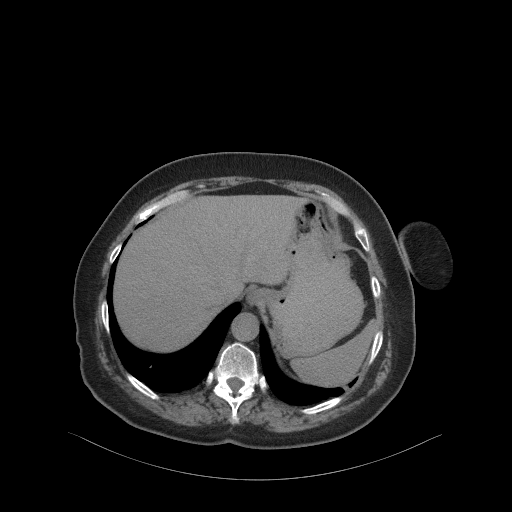

Generated VENOUS CT scan (A→B translation)

No window - Raw intensity values

Lung window (WL -600, WW 1500 β†’ Low βˆ’1350, High +150)

Mediastinum window (WL 40, WW 400 β†’ Low βˆ’160, High +240)